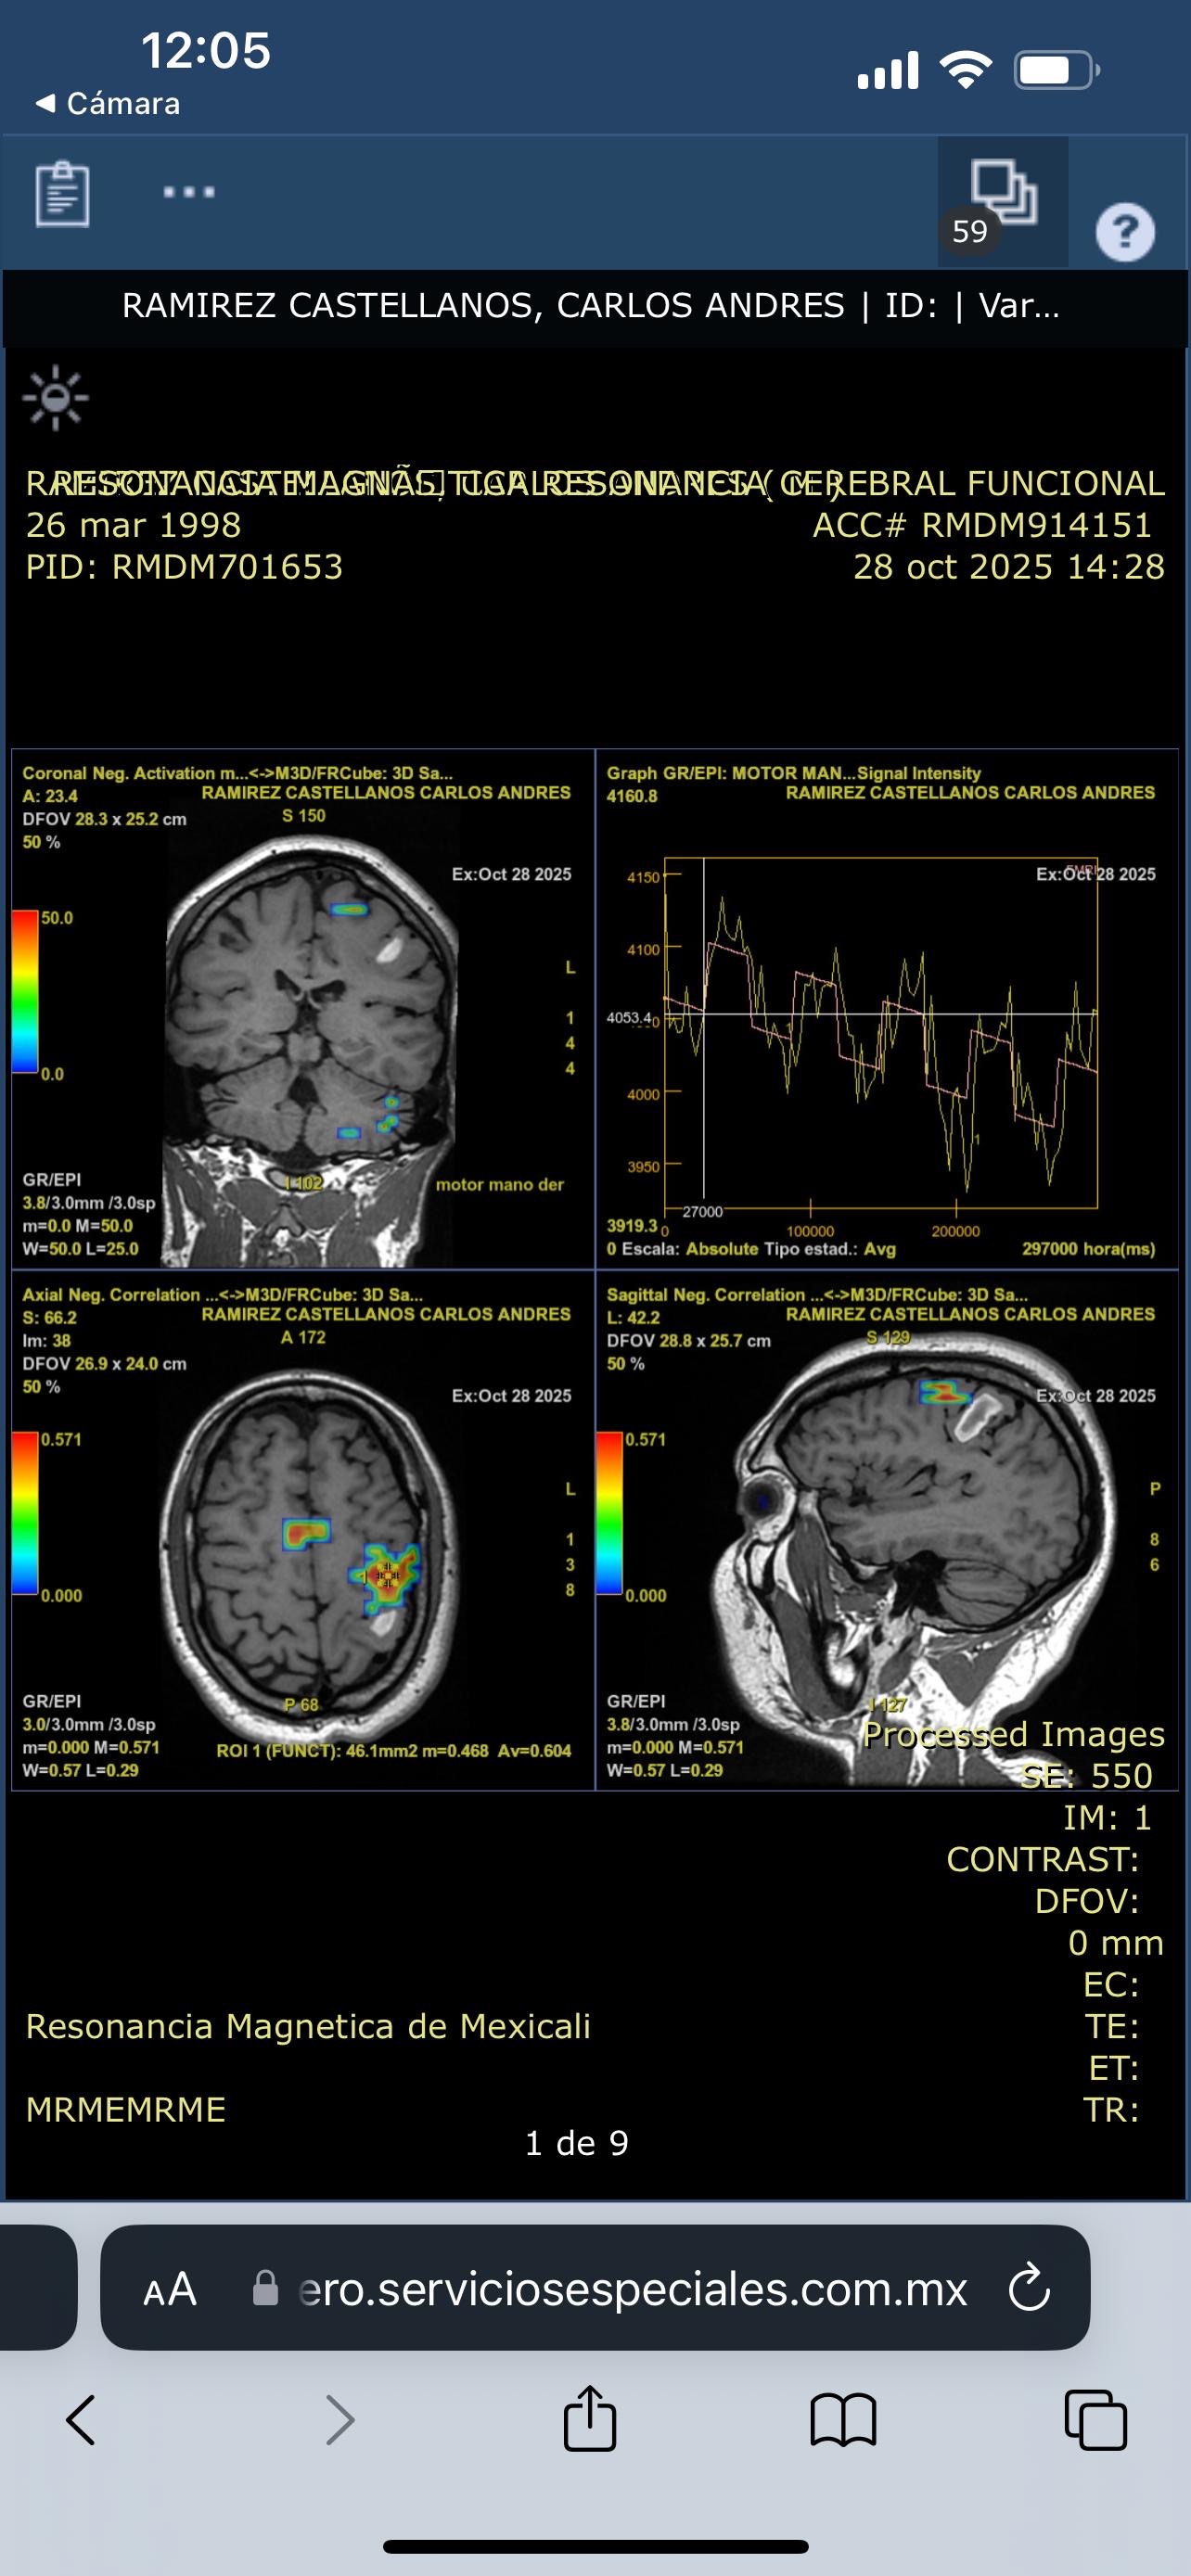

Hoy, lamentablemente, Carlos enfrenta una de las pruebas más difíciles de su vida. Fue diagnosticado con una hemorragia cerebral, una condición grave que avanza rápidamente y requiere una cirugía urgente para salvar su vida.

Today, Carlos is facing one of the toughest battles of his life. He was recently diagnosed with a brain hemorrhage, a serious and rapidly progressing condition that requires urgent surgery to save his life.